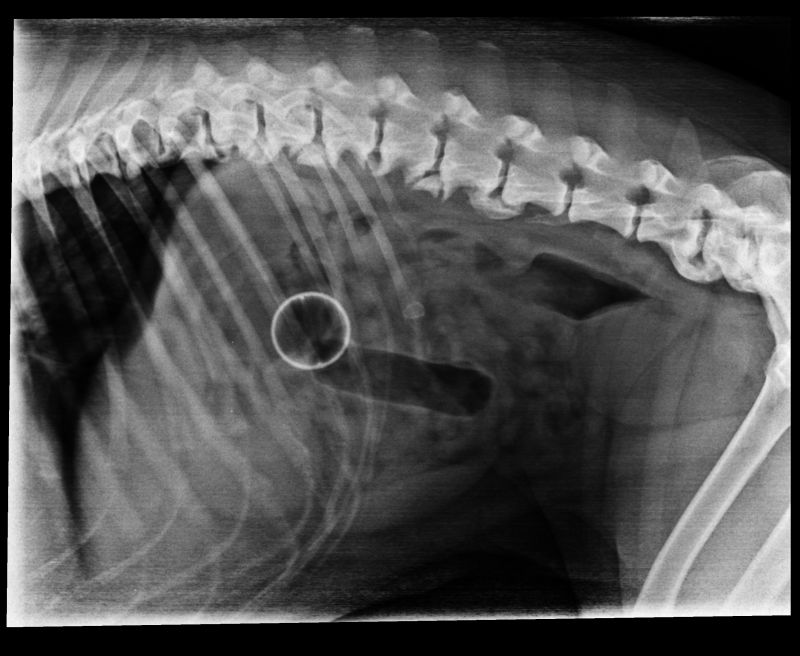

Abnormal Pathology on your pet

Shown on x-ray images which we have taken over the years.

Some interesting patient cases